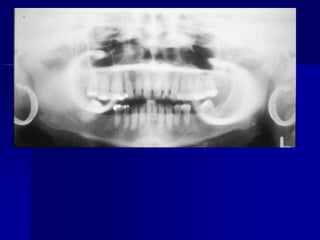

Technique & Projection errorsc. Projection errorsPID alignment artifactIf the PID is misaligned and the x-ray is not centered over the film, a partial image is seen on the resultant radiograph, this partial image is called cone-cut.It appear as a clear area with curved outline.

Technique & Projectionerrorsc. Projection errorsPID alignment artifactIf the PID is misaligned and the x-ray is not centered over the film, a partial image is seen on the resultant radiograph, this partial image is called cone-cut.It appear as a clear area with curved outline.